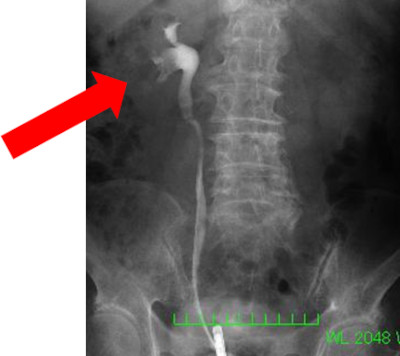

3)排泄性腎盂造影(静脈性尿路造影)

造影剤を静脈注射し、経時的に何回か腹部レントゲン撮影をする検査です。尿の流れに異常があるかどうかがわかり、がんの有無を判定できます。しかし、エコーと同様にCTの性能向上のために必須検査ではなくなりました。